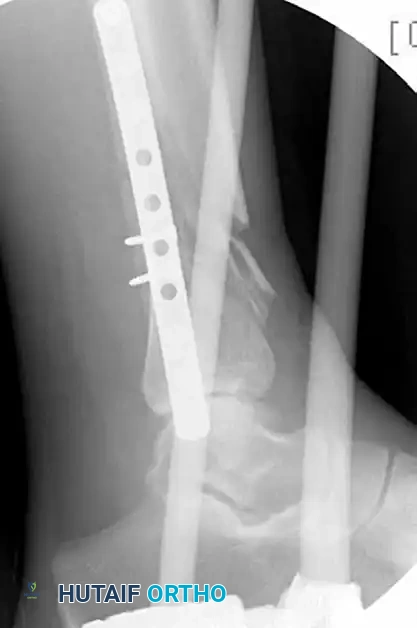

MINIMALLY INVASIVE PLATING OF TIBIAL PILON FRACTURE Surgical Diagram

Figure 54-17 B and C: Application of a uniplanar spanning external fixation and fibular ORIF facilitates indirect reduction of the distal tibial comminution.